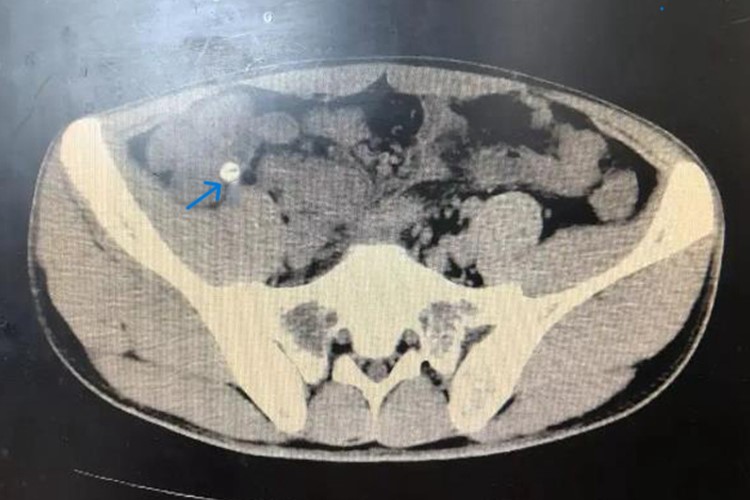

阑尾粪石并不是一种独立的疾病,而是一种病理状态,指粪便或其他不易消化的食物残渣进入阑尾腔内后,由于阑尾的特殊解剖结构(如管腔细、开口小等),在阑尾腔内滞留并逐渐形成块状物,即粪石。

- 阑尾粪石的存在会对阑尾产生一系列不良影响。粪石会阻塞阑尾腔,导致阑尾蠕动异常,管腔梗阻,进而可能继发感染,引发阑尾炎。粪石的存在还可能加重阑尾的炎症反应,使病情恶化。